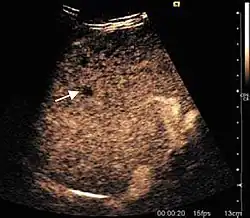

Hepatic hemangioma (2D). The lesion is located in the left hepatic lobe. Note precise delineation, their increased echogenity and the heterogeneous internal structure.

It is the most common liver tumor with a prevalence of 0.4 – 7.4%. It is generally asymptomatic but also can be associated with pain complaints or cytopenia and/or anemia when it is very bulky. It is unique or paucilocular. It can be associated with other types of benign liver tumors. Characteristic 2D ultrasound appearance is that of a very well defined lesion, with sizes of 2–3 cm or less, showing increased echogenity and, when located in contact with the diaphragm, a "mirror image" phenomenon can be seen. When palpating the liver with the transducer the hemangioma is compressible sending reverberations backwards. Doppler exploration reveals no circulatory signal due to very slow flow speed. CEUS investigation has real diagnosis value due to the typical behavior of progressive CA enhancement of the tumor from the periphery towards the center. The enhancement is slow, during several minutes, depending on the size of hemangioma and on the presence (or absence) of internal thrombosis. During late (sinusoidal) phase, if totally "filled" with CA, hemangioma appears isoechoic to the liver. Deviations from the above described behavior can occur in arterialized hemangiomas or those containing arterio-venous shunts. In these cases, differentiation from a malignant tumor is difficult and requires other imaging procedures, follow up and measurements of the tumor at short time intervals.[4]